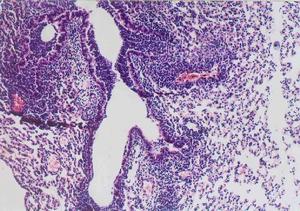

支原體、 衣原體感染人體後,首先侵入柱狀上皮細胞並在細胞內生長繁殖,然後進入單核巨噬細胞系統的細胞內增殖。由於 支原體、 衣原體在細胞內繁殖,導致感染細胞死亡,同時尚能逃避宿主 免疫防禦功能,得到間歇性保護。支原體、 衣原體的致病機理是抑制被感染細胞代謝,溶解破壞細胞並導致 溶解酶釋放,代謝產物的細胞毒作用,引起 變態反應和 自身免疫。

支原體、 衣原體在女性生殖道最常見的侵犯部位是子宮頸,由此而上蔓延可引起子宮內膜炎、輸卵管炎、 盆腔炎,也可引起 急性尿道炎和 前庭大腺炎。孕婦如有 支原體、 衣原體感染,分娩時胎兒經過產道可引起 新生兒眼炎和 肺炎。